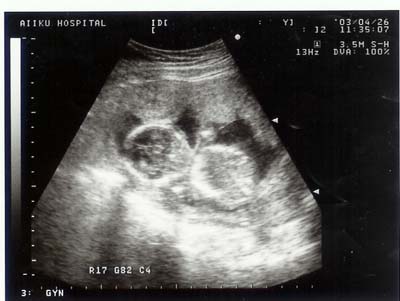

平成15年4月26日(土) 17週目

愛育へ。今日から検査はエコーになる。

見にくいって。

写真は全く2頭身だ。

今回はエコーによる映像だそうです。

何故か「17週の5」になりました。育ちすぎ??